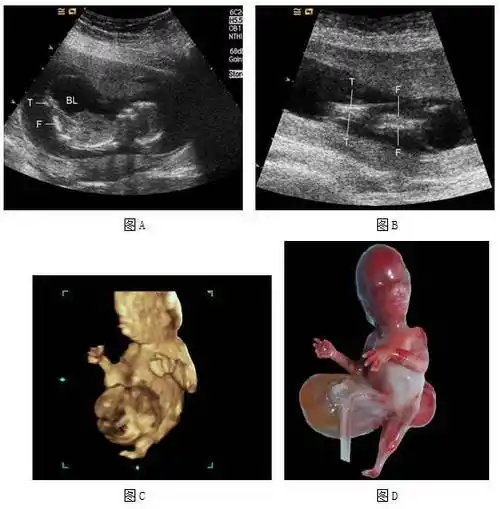

图11 13周5天人体鱼序列征,开放性脊柱裂,巨膀胱 胎儿矢状切面二维(图